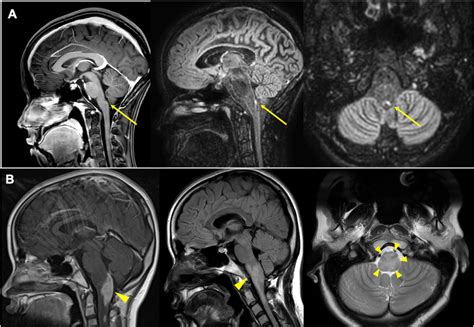

To appreciate how the Area Postrema Vomiting Center functions, it is essential to understand its anatomical location. It is situated in the medulla oblongata, specifically within the dorsal portion of the caudal brainstem. This area is classified as one of the circumventricular organs. Because these organs lack the tight junctions characteristic of the blood-brain barrier, they are considered "leaky" windows that allow the brain to monitor the systemic circulation directly.

The Area Postrema contains a dense network of fenestrated capillaries and specialized neurons. These neurons are highly sensitive to various neurotransmitters and circulating toxins. When substances such as chemotherapeutic agents, bacterial toxins, or certain drugs reach this region, the neurons fire, sending signals to the nearby Nucleus Tractus Solitarius (NTS). The NTS then coordinates the complex motor patterns required for vomiting, involving the diaphragm, abdominal muscles, and gastrointestinal tract.